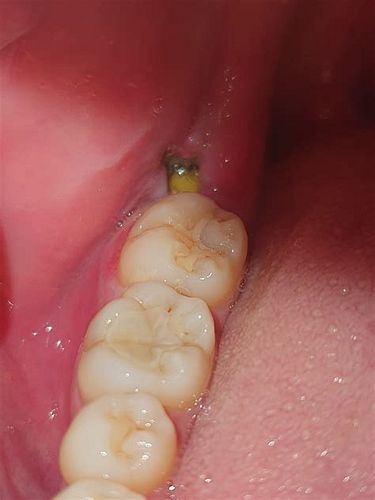

사랑니 통증은 보통 사랑니가 나는 과정에서 잇몸이 부풀거나 염증이 생기면서 발생합니다. 또한 사랑니 주변에 음식물이 끼어 세균 감염이 쉽게 일어나 통증과 붓기, 입 냄새 등 여러 증상을 유발할 수 있습니다. 매복된 사랑니나 기울어져 난 사랑니는 잇몸 염증과 앞 어금니 충치를 유발할 가능성이 높아 통증이 더 심해질 수 있습니다.

- 매복사랑니가 앞 어금니를 밀거나 충치를 일으켜 통증

매복된 사랑니가 앞으로 기울어 있으면, 앞 어금니 뒤쪽 면에 음식물이 쉽게 끼어 충치(치아우식증)가 발생하기 쉽습니다. 이 충치가 진행되면 통증이 나타나고, 충치가 심해지면 앞 어금니의 신경 손상과 통증, 심한 경우에는 앞 어금니의 상실로 이어질 수 있습니다. 또한 매복 사랑니가 주변 잇몸과 뼈에 염증을 유발하면, 앞 어금니 주위의 골 손실과 잇몸 손상도 발생해 치아 지지력이 약해질 수 있습니다.